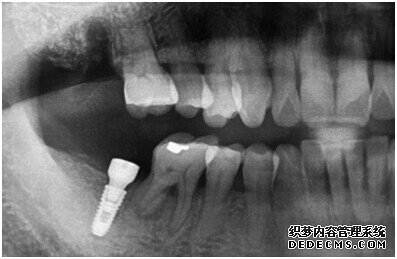

成功植入种植体后的效果图

种植体成功植入后的CT效果图

整个种植牙完成后的效果图

种植牙整个过程完成后,刘女士非常满意自己的牙齿,并且表示以后一定会遵照医生的嘱咐好好注意自己的口腔健康,每晚一定会好好刷牙,饭后漱口,当然也会注意保护这颗种植牙!